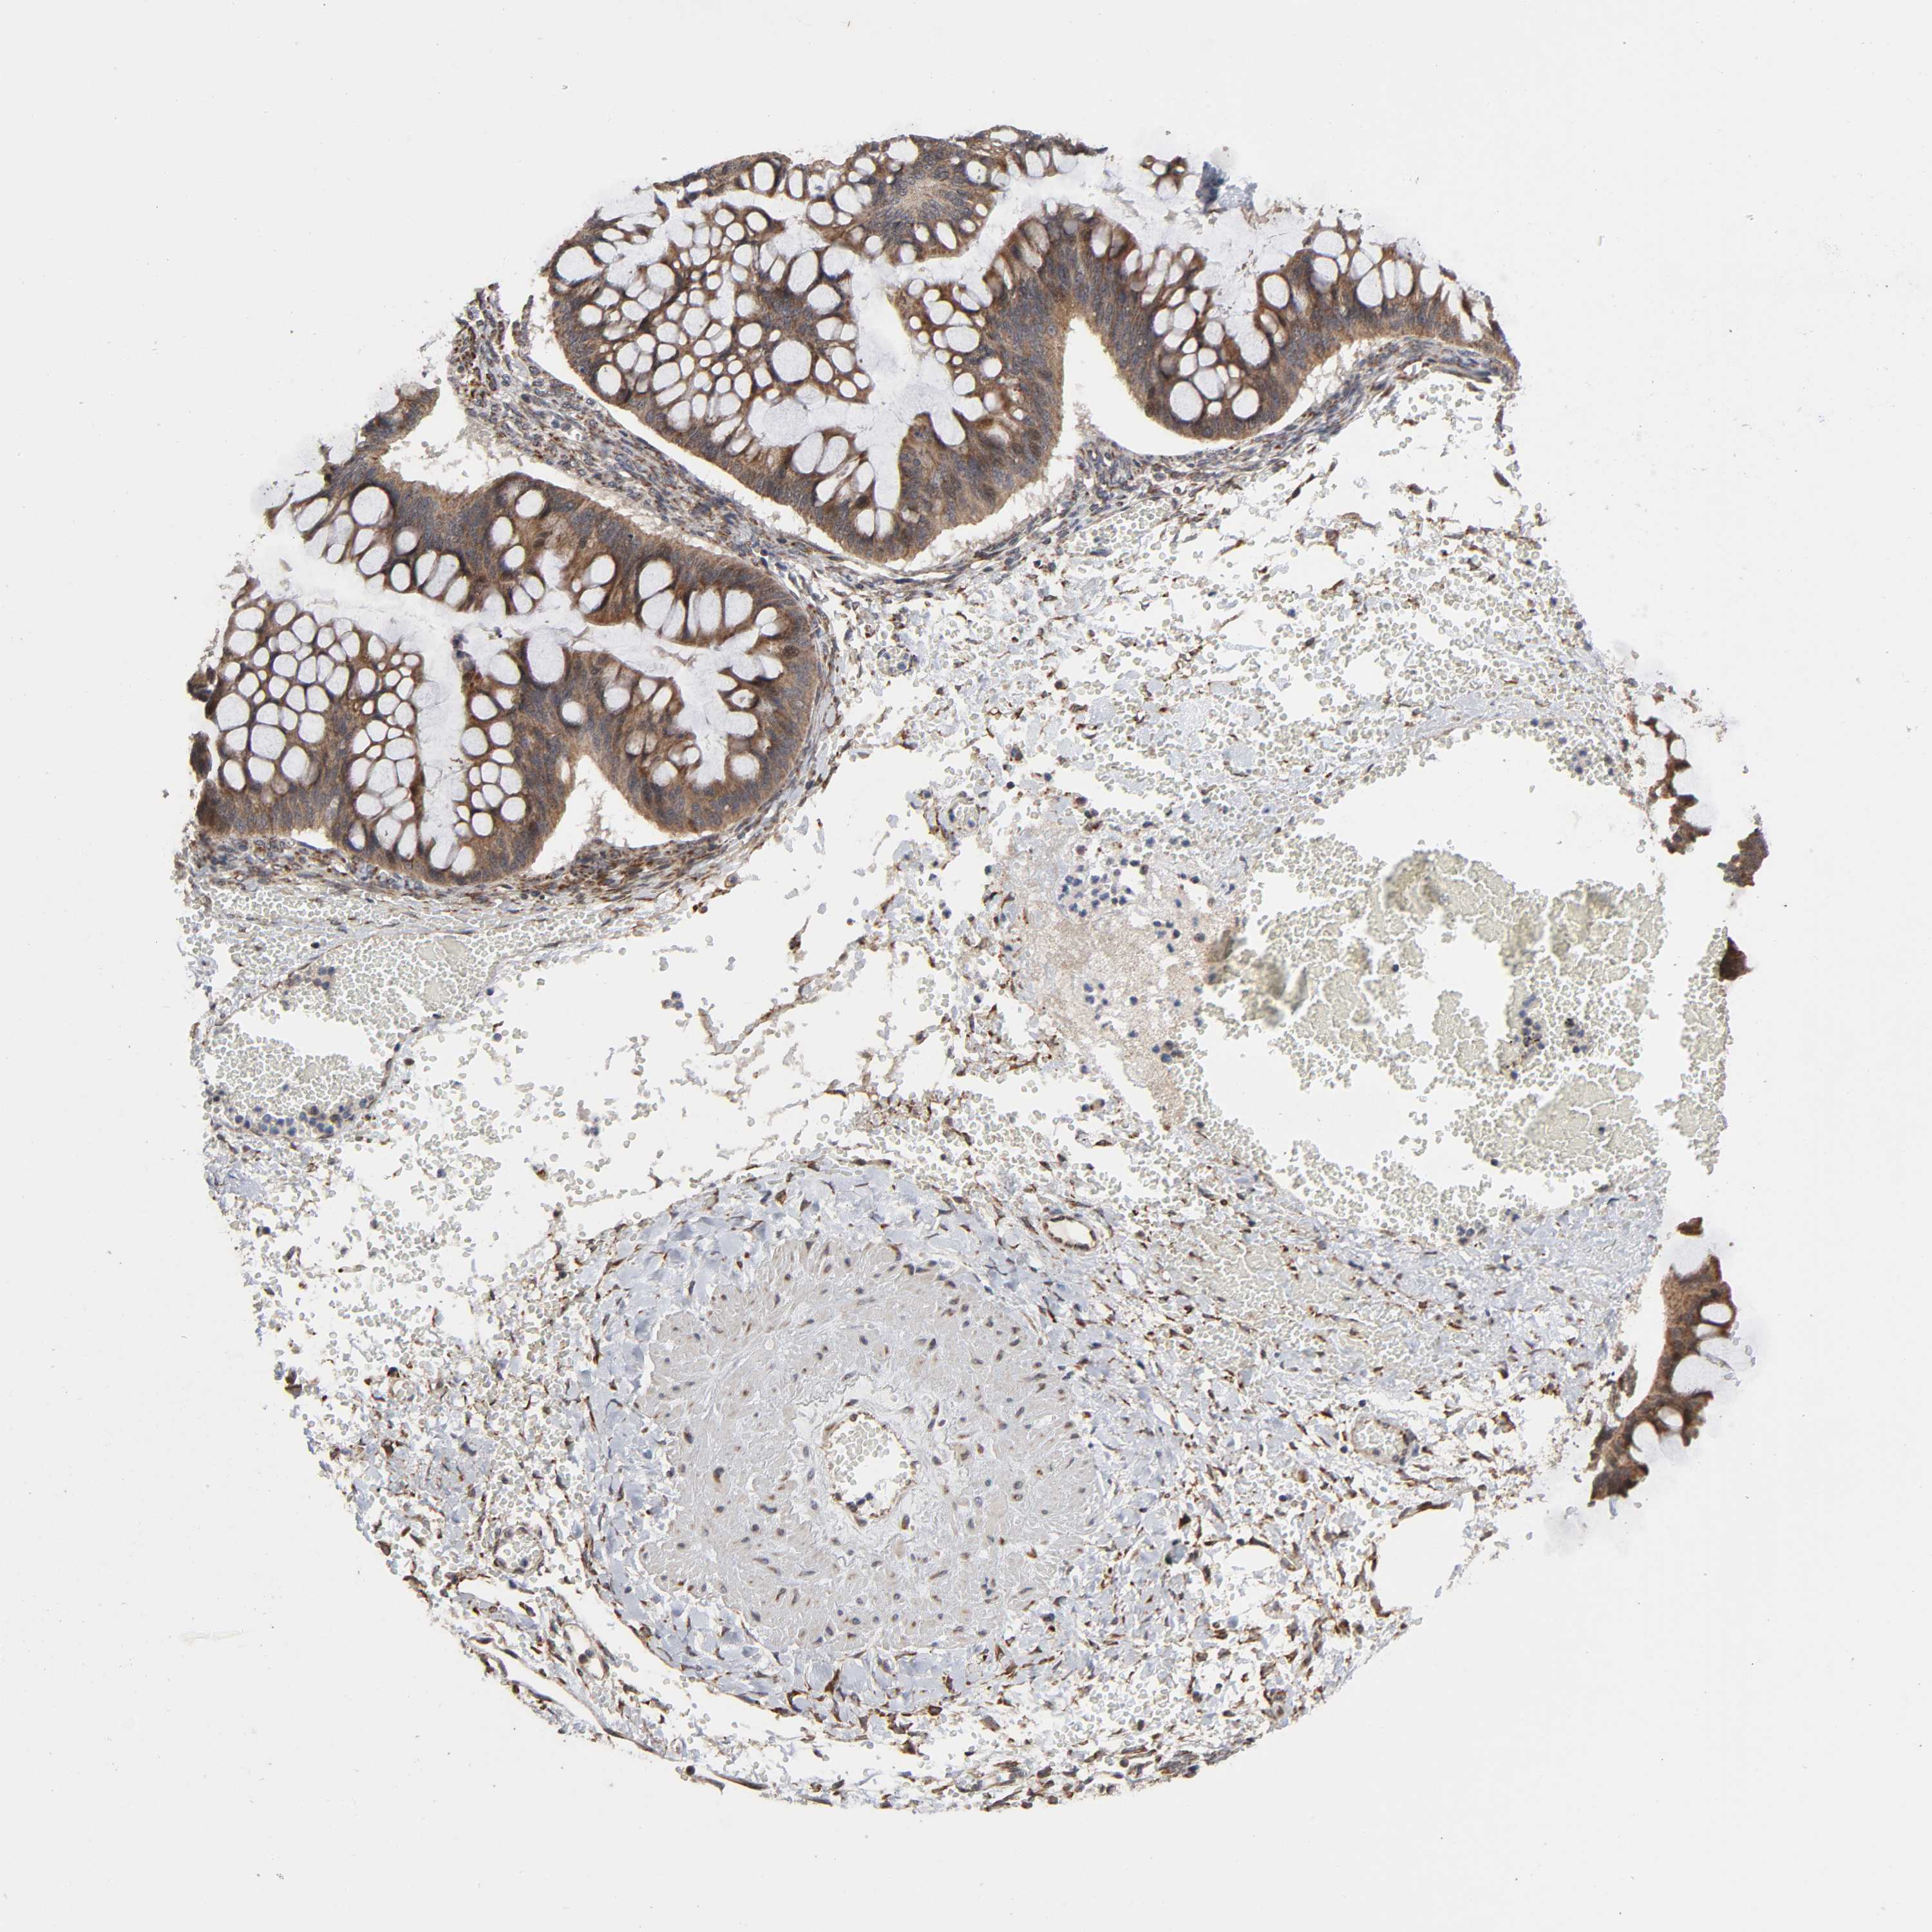

OVARIAN CANCER - Protein expressioni

A mouse-over function shows sample information and annotation data. Click on an image to view it in a full screen mode. Samples can be filtered based on level of antibody staining by selecting one or several of the following categories: high, medium, low and not detected. The assay and annotation is described here.

Note that samples used for immunohistochemistry by the Human Protein Atlas do not correspond to samples in the TCGA dataset.

Antibody stainingi

Antibody staining in the annotated cell types in the current human tissue is reported as not detected, low, medium, or high, based on conventional immunohistochemistry profiling in selected tissues. This score is based on the combination of the staining intensity and fraction of stained cells.

Each image is clickable and will lead to virtual microscopy that enables deeper exploration of all samples and also displays staining intensity scores, fraction scores and subcellular localization as well as patient and tissue information for each sample.

Antibody HPA004014

Staining

High

Medium

Low

Not detected

Intensity

Strong

Moderate

Weak

Negative

Quantity

>75%

75%-25%

<25%

None

Location

Nuclear

Cytoplasmic/membranous

Cytoplasmic/membranous,nuclear

Carcinoma, endometroid